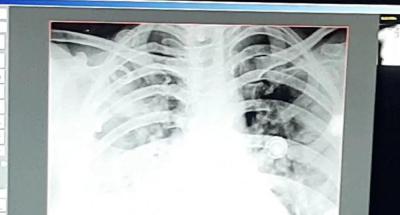

कोरोना व्हायरसच्या दुसऱ्या लाटेने थैमान घातलं आहे. अशात राजस्थानच्या कोटामधून एक धक्कादायक केस समोर आली आहे. इथे केवळ २४ तासात ३२ वर्षीय महिलेचे दोन्ही फुप्फुसं खराब झाले आहेत. फुप्फुसांचे एक्स--रे समोर आले आहेत.

ही केस आहे कोटामधील. येथील ३२ वर्षीय महिलेने ९ तारखेला एक्स-रे काढला तेव्हा ती ठीक होती. १२ तारखेपर्यंत महिल ठीक होती. बीपी, ऑक्सीजन लेव्हल, एक्स-रे सगळं काही ठीक होतं. त्यानंतर १ तारखेला रात्री तिला जरा घाबरल्यासारखं वाटू लागलं होतं.

महिला १३ तारखेला उभीही राहू शकत नव्हती. तिला श्वास घेण्यास त्रास होता होता. ऑक्सीजन लेव्हल चेक केलं तर ९४ होतं. १३ तारखेला सिटी स्कॅन केला तर तिचे दोन्ही फुप्फुसांमध्ये ८० टक्के इन्फेक्शन झालेलं होतं.

हे बघून कोटाचे श्वास रोग तज्ज्ञ डॉक्टर के के डंग हे हैराण झाले. कारण केवळ २४ तासात तिची फुप्फुसे खराब झाली होती. त्यांनी इंदुरच्या एका डॉक्टरसोबत याबाबत चर्चा केली तर त्यांनी सांगितले की, हा नवा स्ट्रेन आहे ज्यामुळे असं झालंय.